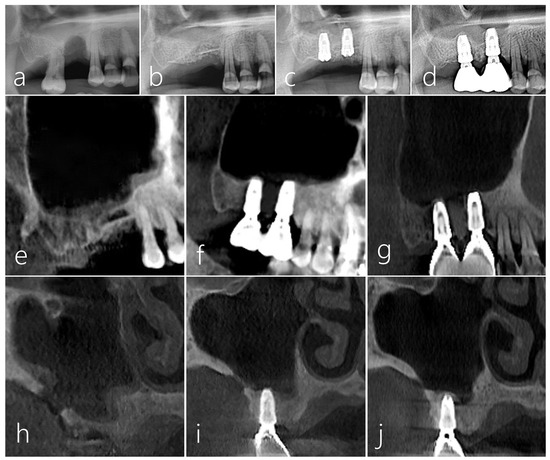

2.1. Case 1

2.2. Case 2

2.3. Case 3

2.4. Case 4